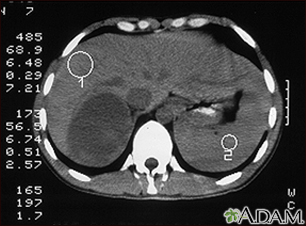

Adrenal Tumor - CT